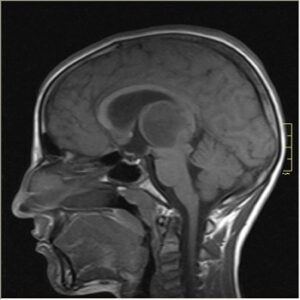

Brain Injuries Caused by Medical Malpractice

Brain injuries vary widely in severity, and range from mild injuries that create temporary problems, to serious injuries that have lifelong implications.

Depending on the severity, brain injuries may cause memory loss, cognitive difficulties, poor concentration, and in serious cases, permanent brain damage or physical disability. Brain injuries are many times the result of accidents such as road accidents or work-related accidents. However, in some cases, a brain injury may be a result of a doctor’s negligence. There are several medical errors that can lead to brain injuries.

Photo credit: commons.wikimedia.org via Google